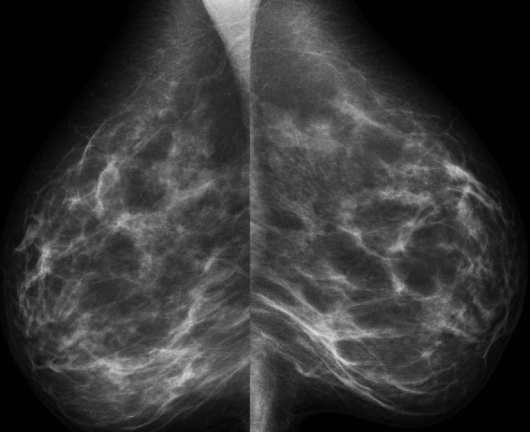

Много жени, които са диагностицирани с рак на гърдата , твърдят, че са открили уплътнение, бучка или тумор , който преди това не били усещали, и се оказало, че е злокачествено. Но излиза, че тази опасна болест има и други, понякога по-ранни, предупредителни „камбанки“.

Разбира се, това не означава, че трябва да спрете да се преглеждате с опипване. 83% от жените, които са били диагностицирани с рак на гърдата, са го открили първо при опипването. Но още малко информация за други симптоми няма да ни навреди. Ако забележите някакви промени в гърдите си, незабавно се консултирайте с вашия лекар .